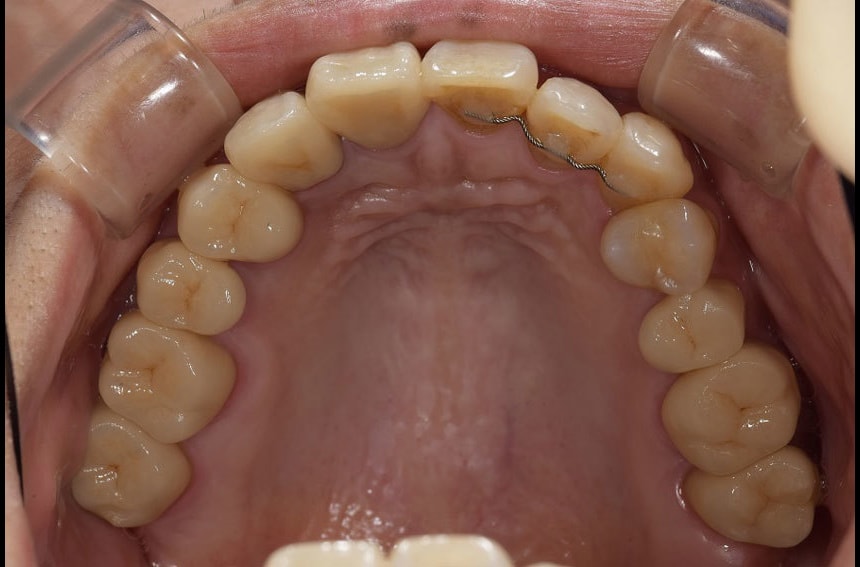

下の歯の治療前後

最小限の矯正治療や過去に治療した銀歯の隙間から虫歯になった歯や神経の再治療を行いました。もう少し修正が必要なのですが、部分矯正も含め長い治療になり、とりあえずはお疲れさまでした。

治療は、僕たちは当然ですが、患者さんにも頑張って頂いて初めてうまくいくものかなとも思います。定期的に通院していただいたり、治療が間延びしないことも治療がうまくいく要因の一つのように感じます。

治療が終了して終わりではなく、維持するためこれからメンテナンスが、始まると思っていただければ幸いです。現状が、できるだけ長期に維持できればと考えています。